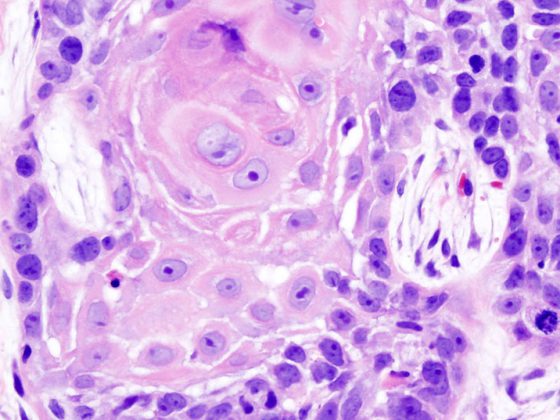

oral_cancer_1_squamous_cell_carcinoma_histopathology

• Plattenepithelkarzinom

Pembrolizumab als Firstline-Therapie senkt Mortalitätsrate